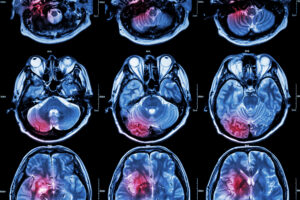

L’Ictus, també anomenat accident vascular cerebral (AVC), atac cerebrovascular, hemiplegia, és un terme que engloba una sèrie de trastorns cerebrovasculars, on podem trobar: l’infart cerebral, l’hemorràgia cerebral i l’hemorràgia subaracnoïdal.

Isquèmic: és el que es produeix amb més freqüència (80% aprox.). Succeeix quan una artèria cerebral s’obstrueix i disminueix el reg sanguini en una zona del cervell. Tot això, origina la mort de neurones per la falta de nutrients i oxigen que van a la sang.

Hemorràgic: Succeeix quan hi ha sang al teixit cerebral o dins dels compartiments cerebrals anomenats ventricles (hemorràgia cerebral), o bé, quan la sang es troba a l’espai que envolta el cervell, conegut com a espai subaracnoide (hemorràgia subaracnoïdal). de sang provoca dany i desplaçament de les estructures cerebrals.